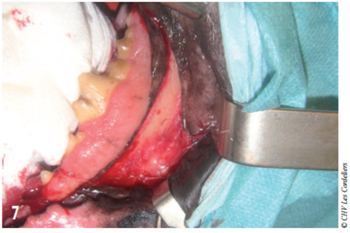

Le chien a été placé en décubitus latéral droit (côté sain). La peau a été tondue autour des babines sur 5 cm de large puis un nettoyage de la zone (bouche y compris) a été réalisé.

Des champs stériles ont été placés sous la tête de l’animal puis autour de la bouche a la jonction cutanéomuqueuse. Un aide opératoire rétractait la commissure des lèvres avec des écarteurs de Faraboeuf ce qui donnait un accès suffisant à la mandibule sans incision des babines (photo 7).

Photo 7 : La rétraction des babines par un assistant permet un accès à la partie caudale de la mandibule. La gencive a été incisée et élevée de l’os.